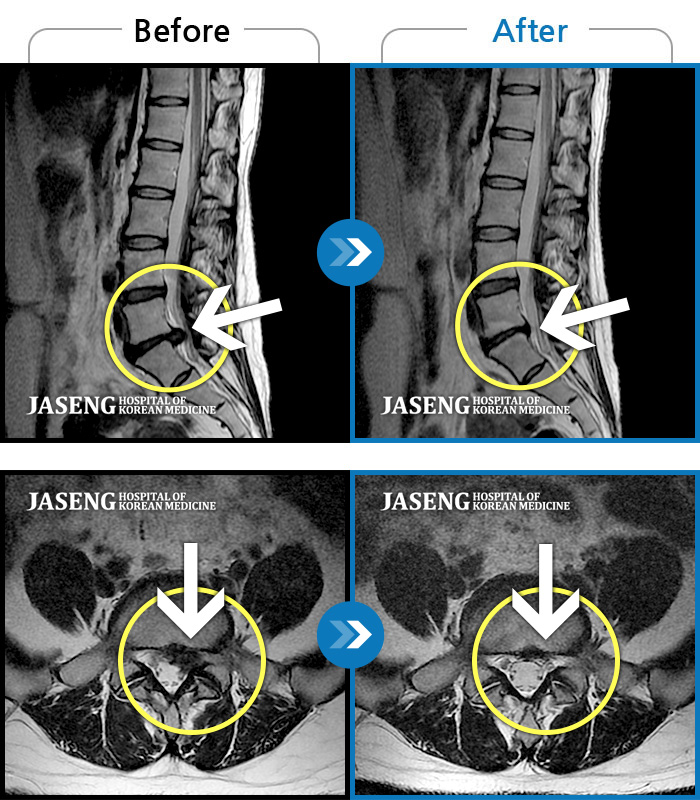

ȯںп Ǹ ǿ ԿǾ, ο ġ ۿ Ƿ ġḦ Ͻñ ٶϴ.